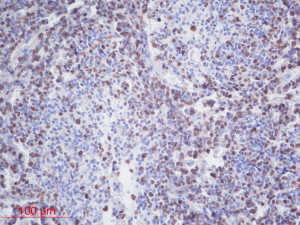

The inclusion criteria were as follows: (I) patients with available pathology (after resection); (II) patients with preoperative MRI data (see Figures 1,2); (III) patients with proven expression of the Ki-67 index by immunohistochemistry; Ki-67 index greater than or equal to 30% is defined as high expression, and Ki-67 index less than 30% is defined as low expression (see Figures 3,4); (IV) patients aged less than 18 years. A total of 271 patients were screened, and 181 patients were excluded due to the following reasons: (I) patients lacking Ki-67 expression by immunohistochemistry (n=96); (II) patients lacking at least one of the following MRI sequences: T1-weighted images (T1W), T2-weighted images (T2W), and contrast-enhanced T1-weighted images (CE-T1W) (n=71); and (III) patients with MR images that had motion or other kinds of artifacts that may affect subsequent segmentation and analysis (n=14). Finally, 90 subjects met the requirements and were included in this study (22 cases of Ki-67 index ≤30 and 68 cases of Ki-67 index >30). Clinical information (age and sex) and tumor characteristics (location, pathological type, and molecular type) are summarized in Table 1.

Ki-67 index is a nuclear antigen related to proliferating cells. Its function is closely related to mitosis and is indispensable in cell proliferation. At present, clinical immunohistochemistry techniques are used to detect the expression of Ki-67 protein, and its positive staining indicates that cancer cells are proliferating actively. It can be used to evaluate the differentiation status of MB cells at the molecular biology level. Compared with traditional pathological classification, this indicator is more objective and easier to implement.